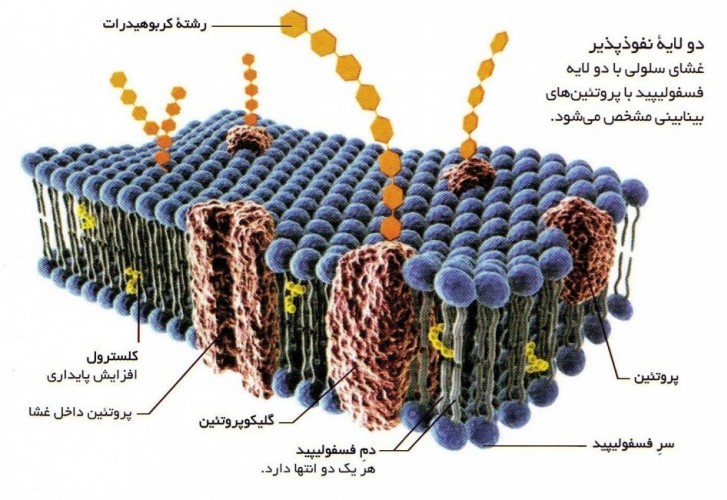

قیمت: 68٬000 تومان - دسته بندی فایل: پاورپوینتپاورپوینت لیپیدها

فروش ویژه پاورپوینت حرفه ای لیپیدها با تخفیف استثنایی فقط 72384 هزار تومان تعداد اسلاید : 37 اسلاید